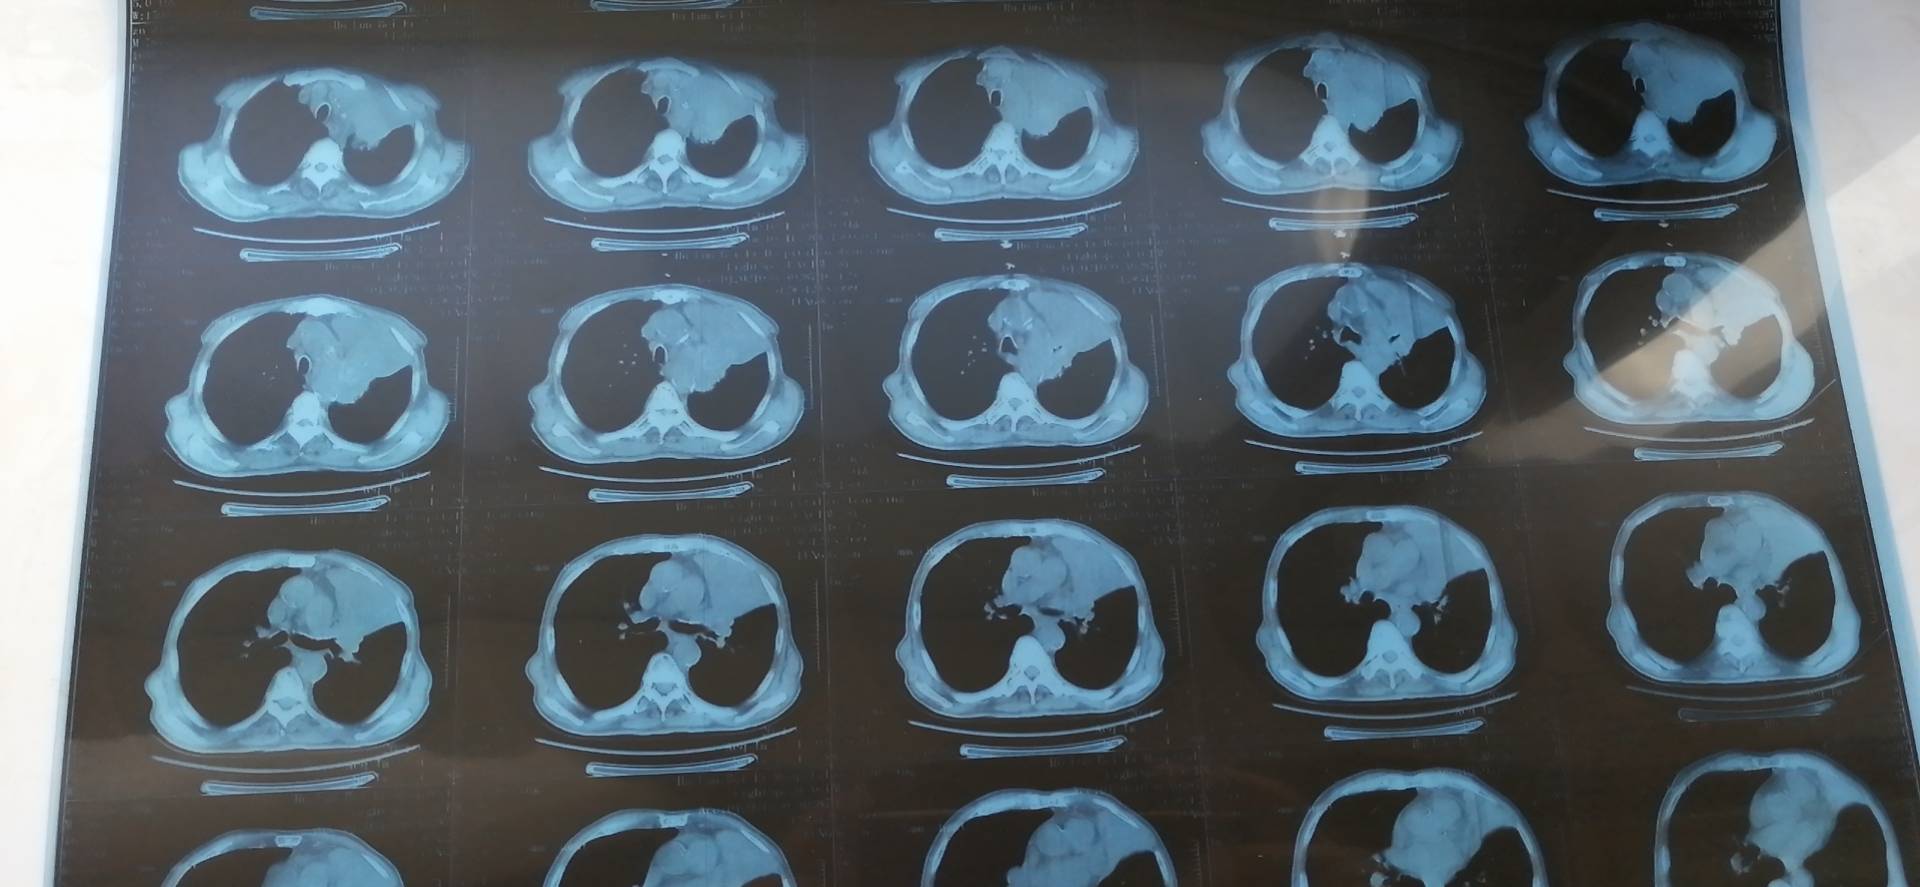

六次化疗加免疫结束了,第一天出各种血检结果,忐忑地站在自助机前打各种报告单,各种结果显示比上次检查结果要好,肿标各项停止了连升,都回到了正常值。第二天打ct胶片,腿还是控制不住地抖,但心里劝自己说第一天的血检结果都很好,这个也应该不会差。一张张胶片缓缓输出来,自己的心跳也越来越快,报告打出来的瞬间,自己冷静了一下才去看它。“4.7*2.6”,没敢相信自己的眼睛,又认真看了一遍的确是,心里的狂喜已经无法自制了。两年前确诊的时候是4.6*6,后期发展出现肺不张之后已经连成了一片白,最近一年的ct都已经不报肿瘤大小了。

感觉自己是一路小跑去找医生的,在医生那得到了肯定的结果:肿瘤缩小大半,胸腔积液消失,效果非常棒,下次撤掉化疗药,单免疫。

图片

治疗前后对比